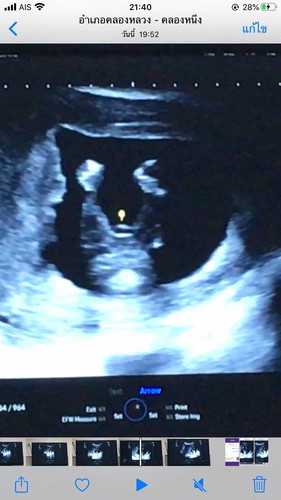

แบบนี้ ผช หรือ ผญ ค่ะ ในใจอยากได้ลูกสาว

หมอบอกเพศไหนคะ ไม่ค่อยเเน่ใจเท่าไหร่ อาจจะหญิงค่ะ